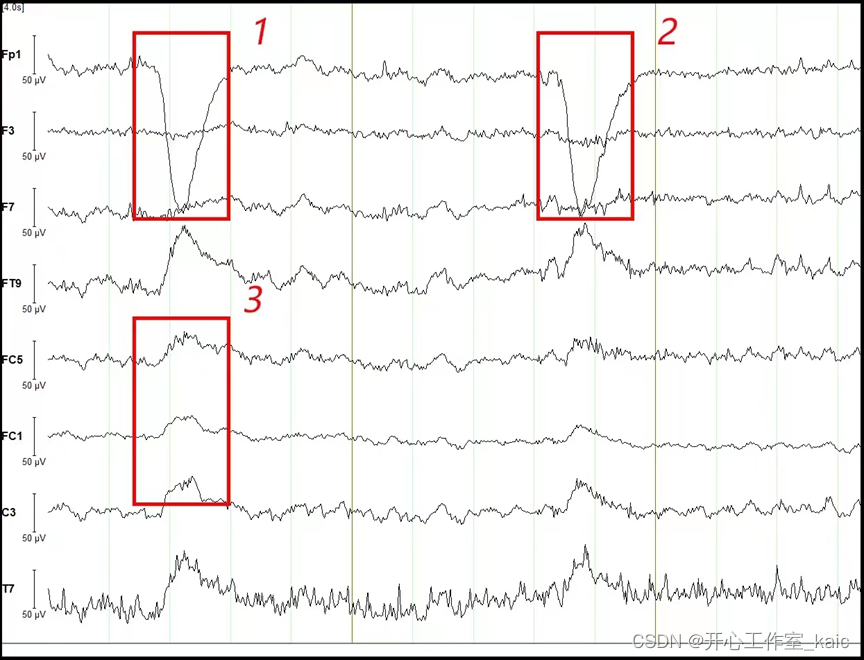

在道路交通安全领域,疲劳驾驶是一种常见的交通安全隐患。现有数据统计,全球每年有大约21%的重大交通事故与疲劳驾驶有关,疲劳驾驶成为了诱发交通事故的主要原因之一,造成了重大的经济损失和人员伤亡[1]。因此,对驾驶员的疲劳程度进行定量分析并实时检测驾驶员的疲劳程度尤为重要。为了应对这一问题,研究人员提出了采用基于脑电功率的疲劳驾驶检测研究来检测驾驶员疲劳状态的方法。本文中采用的数据集是上海交通大学吕宝粮教授等人成立的仿脑计算与机器智能研究中心所测量的SEED-VIG数据集[2]。此数据集是在一个模拟驾驶系统内来收集EEG和EOG数据,通过LCD屏幕实现笔直、单调的驾驶道路,而此种场景更容易是受试者进入疲劳驾驶的状态。通过对数据集进行预处理分析和特征提取分析得到多通道脑电信号的频谱特征,并计算出信号在不同频(Delta、Theta、Alpha和Beta)上的功率谱密度,并使用auc函数计算每个频带上的面积最后基于采集到的脑电信号,建立了基于支持向量机(Support Vector Machine,SVM)的机器学习模型进行疲劳检测。实验结果表明,当大脑从清醒状态进入疲劳状态,枕叶区和颞叶区的Beta波和Delta波的功率谱密度有明显下降,Theta波和Alpha波的功率谱密度明显增强。

Fatigue driving is a common traffic safety hazard in the field of road traffic safety. According to the existing statistics, about 21 % of major traffic accidents worldwide are related to fatigue driving every year. Fatigue driving has become one of the main causes of traffic accidents, causing significant economic losses and casualties. Therefore, it is particularly important to quantitatively analyze the fatigue degree of the driver and detect the fatigue degree of the driver in real time. In order to deal with this problem, researchers have proposed a method to detect the driver 's fatigue state based on EEG power. The data set used in this paper is the SEED-VIG data set measured by the Center for Imitation Brain Computing and Machine Intelligence Research established by Professor Lv Baoliang and others from Shanghai Jiao Tong University [2]. This dataset collects EEG and EOG data in a simulated driving system, and realizes a straight, monotonous driving path through the LCD screen, which is more likely for the subject to enter the state of fatigue driving. The spectral characteristics of multi-channel EEG signals are obtained by preprocessing analysis and feature extraction analysis of the data set, and the power spectral density of the signals at different frequencies ( Delta, Theta, Alpha and Beta ) is calculated, and the area of each frequency band is calculated by using the auc function. Finally, based on the collected EEG signals, a machine learning model based on support vector machine ( SVM ) is established for fatigue detection. The experimental results show that when the brain enters the fatigue state from the awake state, the power spectral density of Beta and Delta waves in the occipital and temporal lobes decreases significantly, and the power spectral density of Theta and Alpha waves increases significantly.

3.2 脑电信号预处理

3.2.3 去除伪迹

(3)基于脑电图(Electroencephalogram,EEG)信号检测

通过长期实验从中得出结论:被试的很多的人体状态信息都包含在脑电波中。从这些生理信息中可提取出很多关键的特征参数,如果选用合适的脑电特征参数进行综合分析,那么健康的驾驶状态和长期疲劳驾驶的状态就可以清晰地区分辩开来。Wang等人把计算功率谱密度(Power Spectral Density,PSD)与计算样本熵(SampEn)算法相融合,融合后发明了以脑电图(EEG)信号为基础的检测方法对实际情况下的驾驶员生理萎靡检测是客观及时有效的,数据显示模仿真实驾驶环境中记载的时间与预测驾驶员疲惫的反应时间相同,证明了这种检测方法是能客观地反应驾驶员的生理状态[12]。刘天娇等人采集21名被试驾驶状态的脑电信号,使用数据功率谱分析的方法,探究驾驶员主动疲劳与脑电指标的关系,研究结果表明:在高速公路的复杂驾驶任务中,驾驶员脑电合并指标呈现下降趋势,同时,与驾驶员主观疲劳程度有显著的正向拟合关系,拟合解释率达50%[13]。